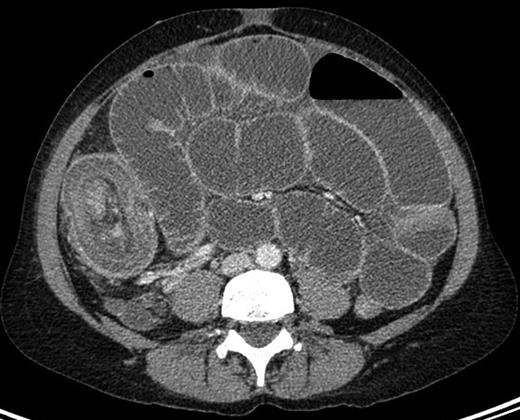

She represented one week later with severe abdominal pain associated with vomiting, poor oral intake and not opening her bowels or passing flatus for one week. On this presentation, a small bowel obstruction with multiple air fluid levels was evident on abdominal x-ray. A CT abdomen was performed, which demonstrated a target-shaped soft tissue mass pathognomonic of intussusception (as shown in Fig. 1).

CT image showing the ‘multiple concentric rings’ sign with the central cylinder representing the canal and wall of the intussusceptum; the middle cylinder representing the mesenteric fat and the other cylinder the returning intussusceptum and the intussuscipiens.